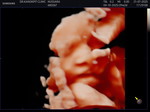

ปวดจิมิ ท้องปั้นบ่อยเป็นอันตรายมั้ย เจ็บก้นกบเเละหน้าอกเป็นอันตรายต่อทารกมั้ย

ถ้าเจ็บถี่ขึ้นหรือมีเลือด น้ำเดิน ให้ไปโรงพยาบาลทันที อาจเป็นสัญญาณใกล้คลอด แต่ถ้าไม่ถี่และทารกดิ้นปกติ